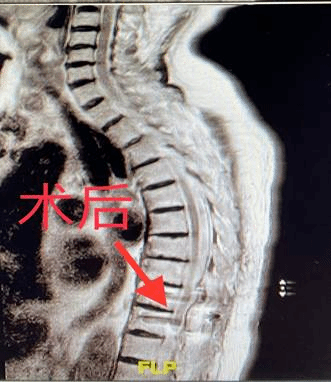

于大娘入院后,王岩松教授、王义文主治医师经过详细询问病史、系统体格检查,完善影像学检查,明确患者诊断为“胸椎管内肿瘤、胸脊髓受压、不全性截瘫”。王岩松教授耐心的向患者家属讲解治疗方案,建议彻底切除肿瘤,解决脊髓压迫问题,为脊髓神经功能恢复创造条件,需行胸椎管内肿瘤手术治疗。但患者81岁高龄,心功能较差,且合并多种基础疾病。该手术方式需要在全麻下进行,手术及麻醉风险均极高。

王岩松教授团队组织心内科、神内科、普外科、妇科、泌尿外科、输血科及麻醉科等多学科MDT会诊,经过多次详细缜密的术前讨论,决定为患者行胸椎管内肿瘤手术治疗。在郭艳祥麻醉医师的保驾护航下,王岩松教授带领王义文主治医师仅用时2小时,顺利把椎管内肿瘤彻底切除,手术用时短、术中创伤小、出血少,术后安稳回到病房。困扰于大娘2年的胸椎管内肿瘤难题终于解决,术后第二日患者腰背痛、腹部及双下肢疼痛麻木无力症状明显缓解,术后一周二便功能已基本恢复正常,术后10天,于大娘已能独立离床下地活动。通过系统科学的围术期管理和快速康复理念,老人成功避免了感染、压疮、脊髓缺血再灌注等各项并发症,临出院前最后一次查房时,于大娘激动落泪地说:“王主任,您就是我的救命恩人,给了我第二次生命,以后欢迎您来建三江做客!”。